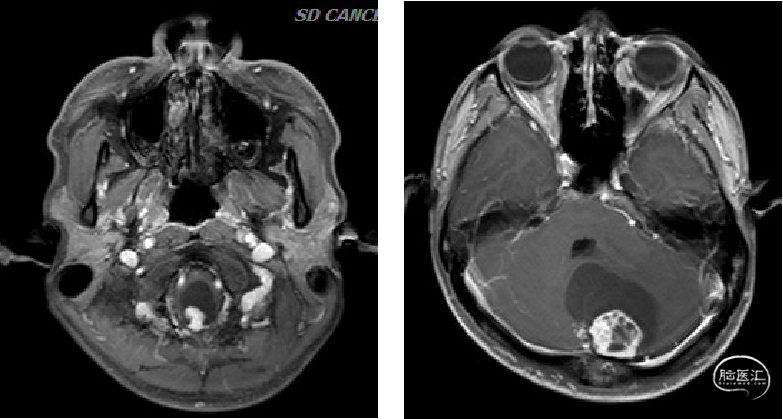

image.png